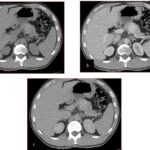

Paciente femenina de 50 años de edad con antecedentes de HTA. Anexo histerectomía total por carcinoma de útero, apendicetomía, colecistectomía, cesárea, resección de tumor basocelular. Derivada de Hospital Regional Dr. Luis Pasteur de Villa María de Córdoba el 21 de marzo de 2021 a Hospital Sanatorio Franchin por cuadro de hipoglicemias severas sintomáticas a repetición, con laboratorios clínicos donde se observó hipoglicemia asociada a hiperinsulinismo; el péptido C se encontraba elevado. Se realizó imágenes (TAC, RMN) que evidenciaban lesión en región de cabeza de páncreas medial con refuerzo arterial, compatibles en primera instancia con insulinoma. Se decide conducta quirúrgica debido a clínica, realizándose el día 27 de abril de 2021 duodeno pancreatectomía, evolucionó con fístula pancreática con requerimiento de octreotide. Posteriormente se realizó seguimiento de la paciente sin evidencia de síntomas de hiperinsulinismo, y en los controles radiológicos no se encontró recurrencia.

Estudio histopatológico reveló tumor neuroendocrino bien diferenciado grado 1, márgenes libres con ausencia de metástasis.

Estudio histopatológico reveló neoplásica de estirpe neuroendocrina bien delimitada.

Ahora bien, como se mencionaba al principio, el estudio ecográfico es de muy baja sensibilidad y se identifique o no la lesión por este estudio, nuestro siguiente paso en el algoritmo diagnóstico de esta lesión es la tomografía. Esta es la prueba no invasiva inicial, con una sensibilidad del 63% al 83%, y detecta del 70% al 80% de los tumores. Esta debe realizarse como un estudio trifásico: fase arterial temprana a los 30 segundos, fase venosa a los 70 segundos, fase tardía de 3 a 5 minutos. La característica de estos tumores por tomografía es que se presentan como una masa sólida que tiene un ávido realce en la fase arterial, cuyo realce se mantiene y se observa más tenue en la fase venosa y en los tiempos tardíos la lesión se homogeniza.

La resonancia magnética es el otro estudio de imagen no invasivo que nos permite la detección de la lesión con una sensibilidad mayor que la de la tomografía, del 85% al 95%, donde los insulinomas presentan un realce tras la administración de contraste con gadolinio y secuencias T1 sin contraste son lesiones hipointensas y en secuencias T2 son hiperintensas.